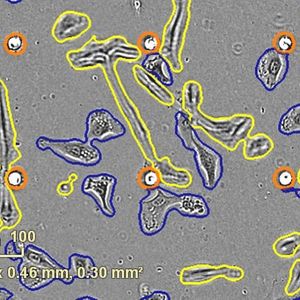

FEB 09, 2024CancerHistopathology describes the process of examining pieces of tissue using a microscope. Light microscopic (LM) exam ...